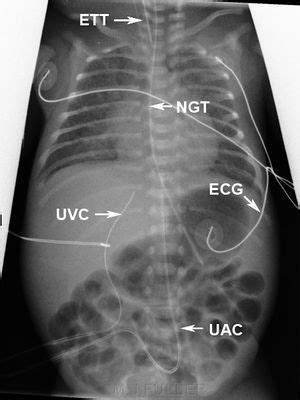

Umbilical Vein Catheterization - WikEM

Umbilical vein catheterization - WikEM www.wikem.org

umbilical vein neonatal uac uvc catheter lines nicu position vs catheters pediatric catheterization xray artery tubes tube radiograph nursing baby